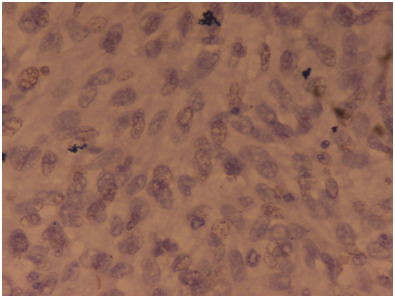

A 22-year-old married female presented in the gynecologic outpatient department with the chief complaints of difficulty in breathing and pain in the lower abdomen since a fortnight. She also complained of fever on and off since 20days with associated weight loss, weakness and fatigue. On physical examination, a mass was felt in the suprapubic region, about 20cm×15cm in size, firm and immobile on palpation. Her laboratory investigations revealed mild microcytic hypochromic anemia and leukocytosis (13,500cells/μl). Liver and kidney functions were normal. Urine analysis revealed no pathology. Pelvic ultrasound and computed tomography revealed a huge and heterogeneous pelvic mass containing solid and cystic areas with ascites measuring 16x13x9cm. Whole body scan revealed no other abnormality. Ascitic tap smear showed only degenerate cells with no viable malignant cells. Chest x-ray revealed left pleural effusion, which on aspiration cytology showed presence of atypical cells suggesting metastatic adenocarcinoma. The serum CA-125 level was markedly raised (126U/ml). Three cycles of neoadjuvant chemotherapy comprising of paclitaxel and carboplatin was administered to relieve her symptoms of breathing, followed by total abdominal hysterectomy with unilateral salpingo-oophorectomy. Laparotomy revealed an unilateral ovarian mass, grossly measuring 13cm×13cm×7cm in size with glistening white and slightly nodular outer surface. Cut surface showed homogenous grayish white solid and cystic areas along with hemorrhage and necrosis (Figure 1). Microscopically section from the tumor showed malignant fascicles of spindle cells with hyperchromatic and pleomorphic nuclei, 30mitosis/10 HPF mixed with areas of necrosis (Figure 2). Necrotic areas might be the carcinomatous component which was responsive to chemotherapy whereas the mesenchymal sarcomatous component was resistant to therapy. Foci of hemorrhage and cystic degeneration were also seen. Histologically, the major part of the tumor consisted of the sarcomatous component which was Van Geison (VG) positive (Figure 3) and showed weak diffuse vimentin positivity on immuno histochemistry (Figure 4). On the basis of clinical findings, gross and microscopic findings, a diagnosis of carcinosarcoma ovary was made.

Figure 2 Microscopically the section from tumor showed malignant fascicles of spindle cells with hyperchromatic and pleomorphic nuclei, 30 mitosis/10 HPF mixed with areas of necrosis. Haematoxylin & Eosinx40X.